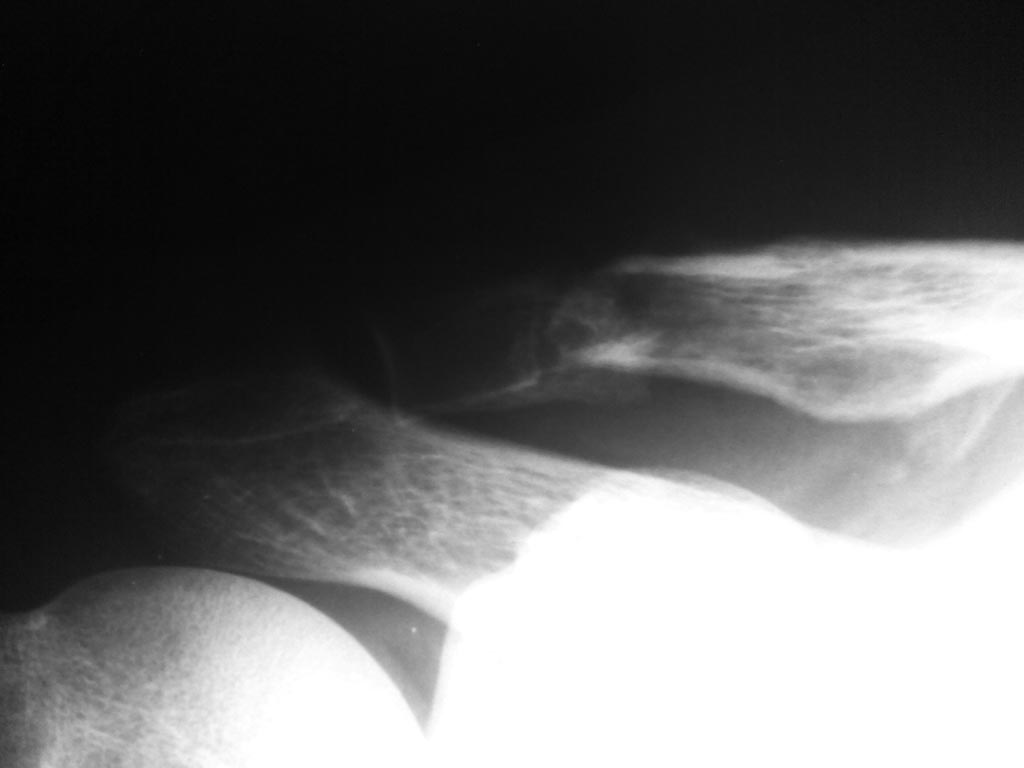

Re: Ложный сустав акромиального конца ключицы

Евгений, добрый день. Файл во вложение есть, что сейчас мы имеем. Собственных варианта 2 оперативное лечение LCP пластиной или консервативное дальнейшее ведение.

Мой вариант: блокируемая пластина, костная (алло- или ауто-) пластика. Гипсовая повязка недели 3-4 для гарантии. Всё ж спорт там какой-то упоминается.

Ну и как вишенка на торте - сравните со здоровой ключицей по форме и длине, чтобы совсем уж идеально восстановить.

Пластину пожёстче выбирайте, я на ключицу часто предпочитаю узкие прямые пластинки для предплечья, если нет нормальных ключичных - они значительно жёстче реконструктивных, меньше вероятность возврата пациента со сломанной пластиной.